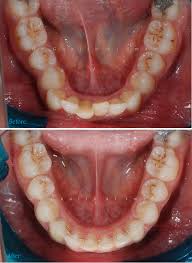

치아교정은 치아를 가지런히 배열하기 위해 진행하는 것입니다. 하지만 공간이 없다면요? 위 사진의 경우 도저히 발치를 하지 않고서는 충분한 공간 확보가 어려워보입니다. (출처: https://www.forbesorthodontics.com/)